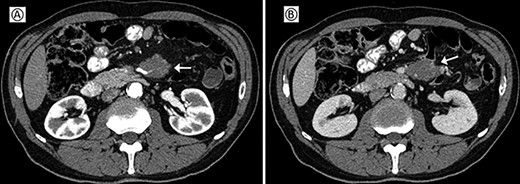

This case involved a 63-year-old man who had a history of hypertension, psoriasis and atherosclerosis. He referred the appearance of a light epigastric pain and general discomfort. Laboratory tests were normal. Abdominal ultrasonography was negative as well as the esophagogastroduodenoscopy and colonoscopy. Abdominal computer tomography (CT-scan) with contrast showed a solid mass of about 42 × 31 mm in the mesenteric adipose tissue, incorporating the distal part of the SMA and the superior mesenteric vein (SMV) (Fig. 1). A fluorodeoxyglucose positron imaging tomography/computed tomography (CT) showed an increased uptake (SUV 5.2) at the level of the mesenteric mass.

Preoperative CT; (A) arterial phase: the arrow shows the neoplastic mass traversed by the superior mesenteric artery. (B) Venous phase: the arrow shows the neoplastic mass in contact with the superior mesenteric vein.